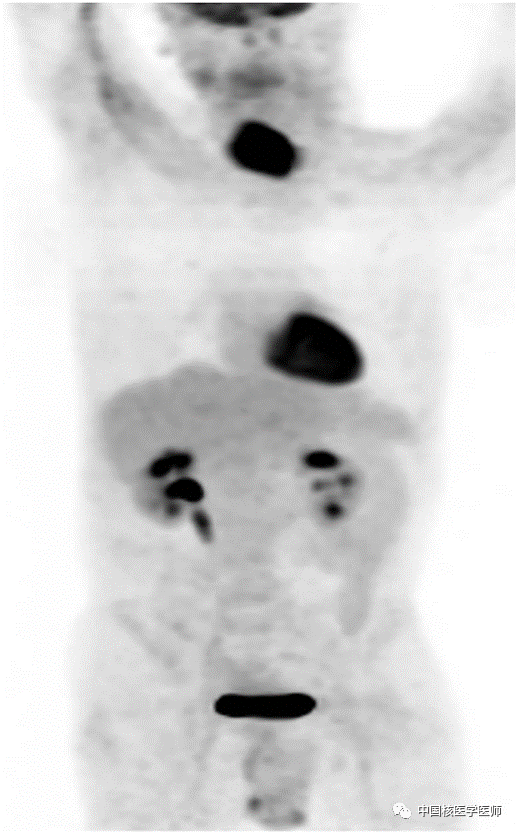

圖3.18F-FDG PET/CT MIP圖顯示未發(fā)現(xiàn)任何轉(zhuǎn)移性病灶。術(shù)后病理組織學(xué)檢查提示在區(qū)域淋巴結(jié)中未見轉(zhuǎn)移。

鱗狀細(xì)胞癌在甲狀舌管囊腫中極為罕見,目前已有3例甲狀舌管囊腫甲狀腺乳頭狀癌的報(bào)道,其中一個(gè)例超聲和CT檢查發(fā)現(xiàn)了這些特征,另外2例報(bào)道是應(yīng)用18F-FDG PET/CT顯示甲狀舌管囊腫內(nèi)發(fā)生乳頭狀甲狀腺癌。還有一個(gè)案例報(bào)告使用了99mTc-MIBI甲狀腺舌管鱗狀細(xì)胞癌的影像學(xué)研究。然而,關(guān)于18F-FDG PET/CT顯像甲狀腺舌管鱗狀細(xì)胞癌似乎僅限于術(shù)后患者。18F-FDG PET/CT可以用于評(píng)估甲狀舌管囊腫是否伴有鱗狀細(xì)胞癌。據(jù)我們所知,沒有人報(bào)道過術(shù)前18F-FDG PET/CT顯像發(fā)現(xiàn)甲狀舌管囊腫伴鱗狀細(xì)胞癌。我們建議對(duì)于已確診的甲狀舌管囊腫伴鱗狀細(xì)胞癌患者,可以使用18F-FDG PET/CT顯像輔助評(píng)估其病變累及范圍。